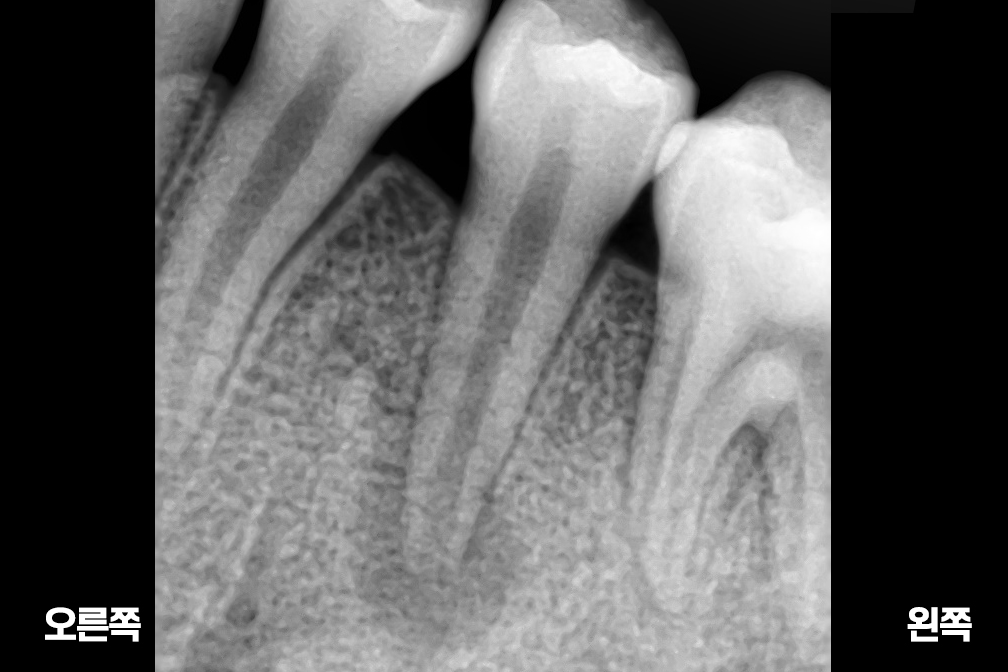

Before 2025년 6월 25일